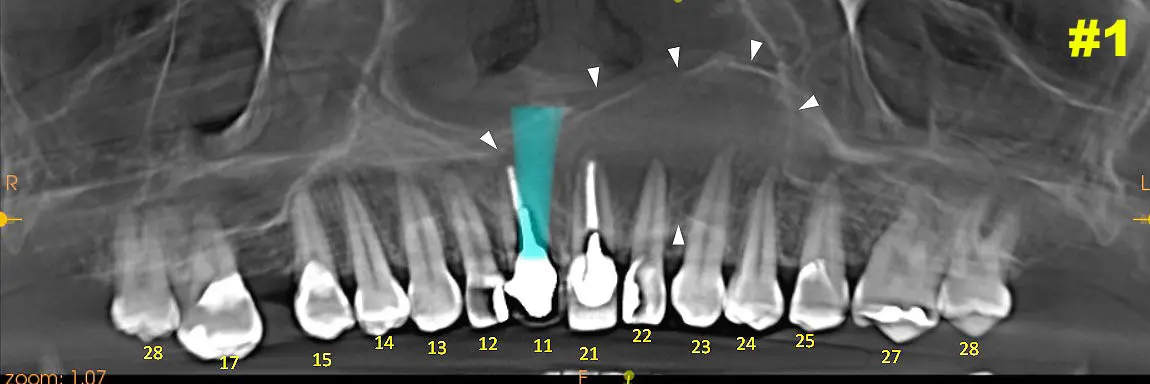

Caso N° 92: Quiste Nasopalatino

Paciente: Femenino, 37 años.

Motivo de consulta: control general y posible colocación de implantes.

​Como resultado en primera Vista panorámica podemos ver imagen de forma redondeada con bordes delimitante y corticalizados con densidad hipodenso la cual se expande desde porción radicular de Pd 21 hasta porción radicular de Pd 24. Imagen 1